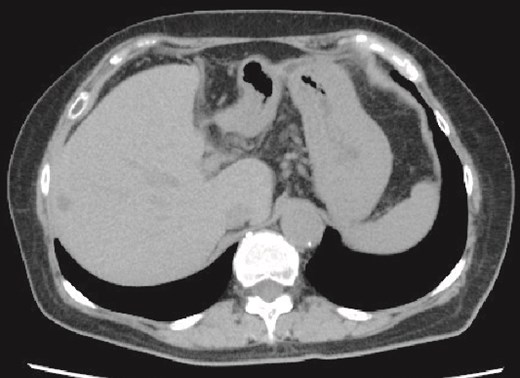

A 71-year-old female had suffered from upper abdominal pain for ~7–8 years. She consulted her primary care physician, and computed tomography (CT) demonstrated a 16-cm hepatic cyst in the left hepatic lobe (Fig. 1a). Although she had no history of peptic ulcer, she had not gotten an upper gastrointestinal endoscopy for decades.

(a) Enhanced CT images findings obtained in the examination by the patient’s primary care physician. A 16-cm hepatic cyst in the left hepatic lobe area was observed. Dotted line: The hepatic cyst. (b, c) Plain CT images findings obtained at the patient’s hospitalization. (b) This axial section shows the large hepatic cyst in left hepatic lobe area, which was collapsed and contained air bubbles. There were no findings of free air or leakage into the peritoneal cavity. Arrowheads: The air bubbles of collapsed large hepatic cyst. (c) A low-density area between the hepatic cyst and the duodenum with a suspicion of a fistulous tract can be seen on this coronal section. Arrows: The low-density area between the hepatic cyst and the duodenum. (d) An abdominal X-ray finding after the percutaneous catheter aspiration of the hepatic cyst with a 7Fr pig-tail catheter (left arrow). Right arrow: The nasogastric tube.